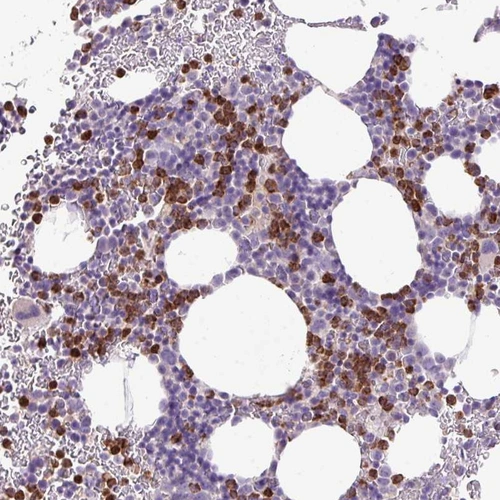

Immunohistochemical staining of human bone marrow shows moderate cytoplasmic positivity in hematopoietic cells.